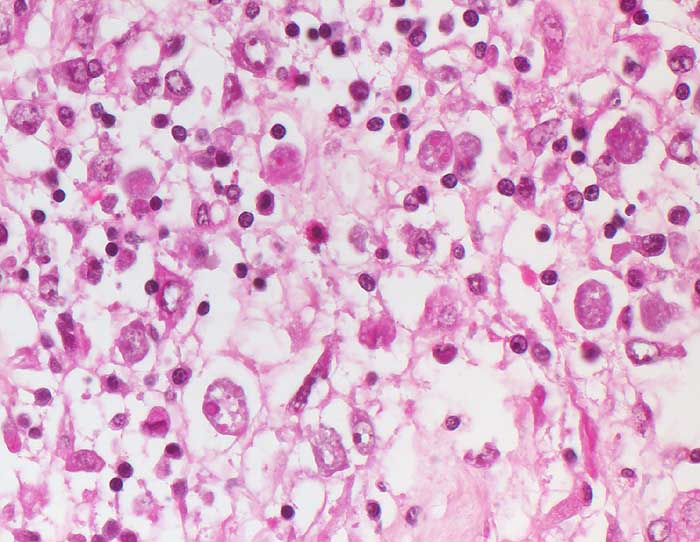

Amöbenkolitis

Entzündung infektiös

Kolon

Pathologischer Befund